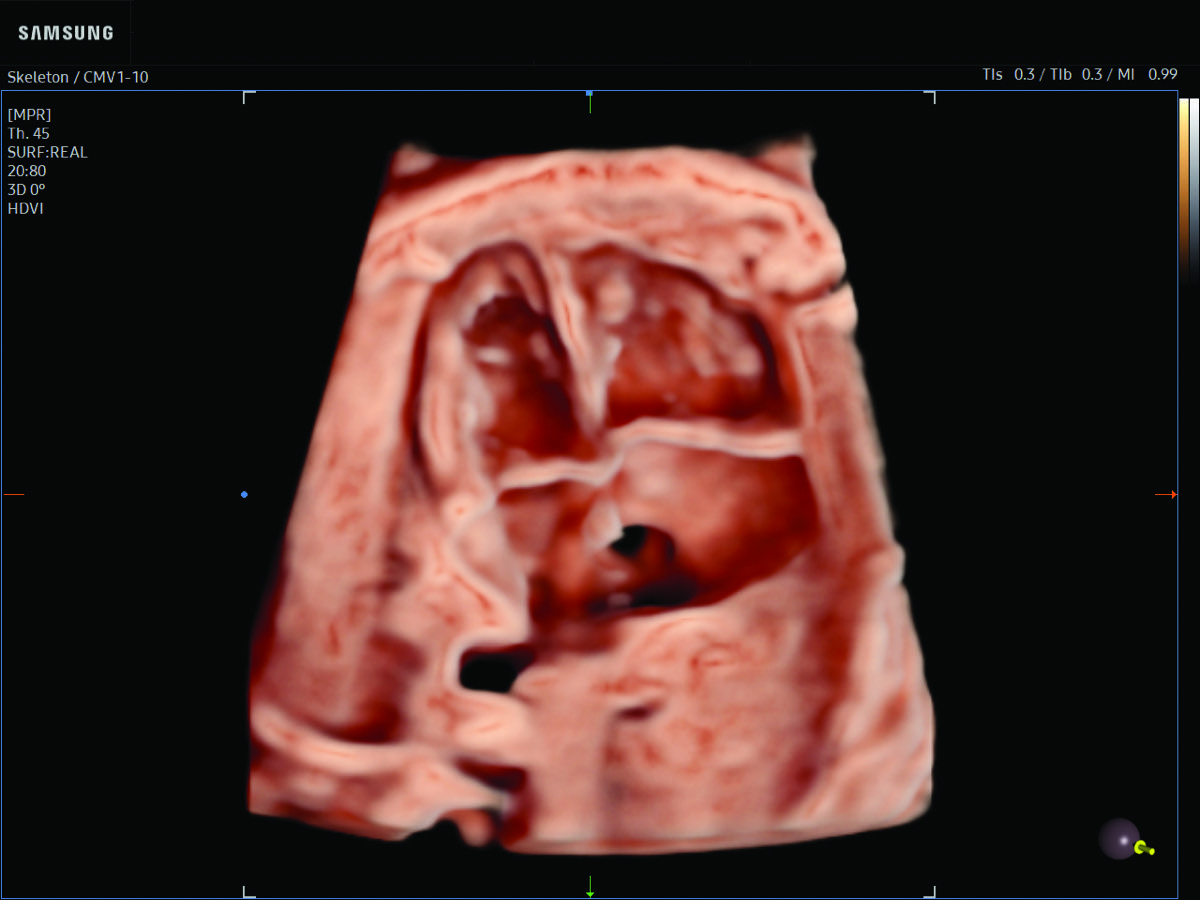

Comprehensive, advanced and expert MFM care for high-risk pregnancies

- Fetal anomalies